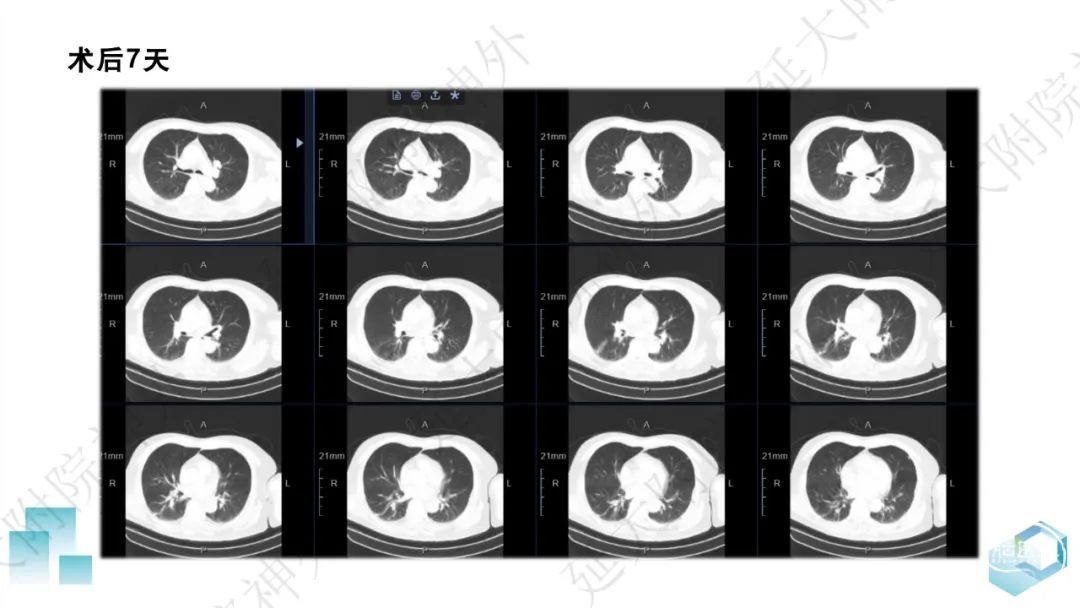

今天为大家分享的是《监测有道丨颅脑创伤-神经重症周刊》第332期,由延安大学附属医院神经外科贾云峰主任医师带来的:左侧基底节区出血破入脑室一例神经内镜下血肿清除术,欢迎阅读、分享。

长期从事神经外科疾病的基础与临床研究。专长于神经急危重症综合治疗、神经内镜脑出血微创手术、脊髓脊柱疾病显微外科微创治疗、颅内及脊髓肿瘤、脑血管病、脑、脊髓先天畸形的微创治疗。参与主持完成科研项目《尼莫地平对脊髓损伤的作用研究》等,获陕西省自然科学优秀论文奖。参与国家卫健委牵头的《自发性脑出血的多中心登记研究》等项目研究及《脑出血患者颅内压监测》《脑出血后脑水肿的治疗》专家共识的制定。以第一作者在国内外发表核心期刊20余篇,SCI收录文章1篇,多次应邀在中华医学会、中国医师协会全国神经外科学年会交流发言。主编及参编著作3部,国家发明专利2项